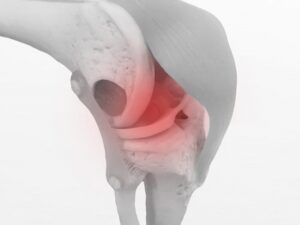

日常生活やスポーツ活動において、「膝のねじれ」や「姿勢の崩れ」を感じる方は少なくありません。こうした関節のアライメント(骨や関節の位置関係)の乱れは、身体の動かし方のクセや筋肉の働き方の不均衡から生じることがあります。特に膝関節は構造的に不安定な部位であり、アライメントが崩れることで負担が集中しやすい場所です。

本研究では、膝関節の「内反角度(いわゆるニーイン)」が大きい女性アスリート28名が対象となりました。膝の内反角度が強い状態は、スポーツ中に膝へ過剰なストレスをかける要因とされ、傷害リスクの高さとも関連すると言われています。

• 単脚ジャンプ動作における膝の内反角度が平均で約6度減少